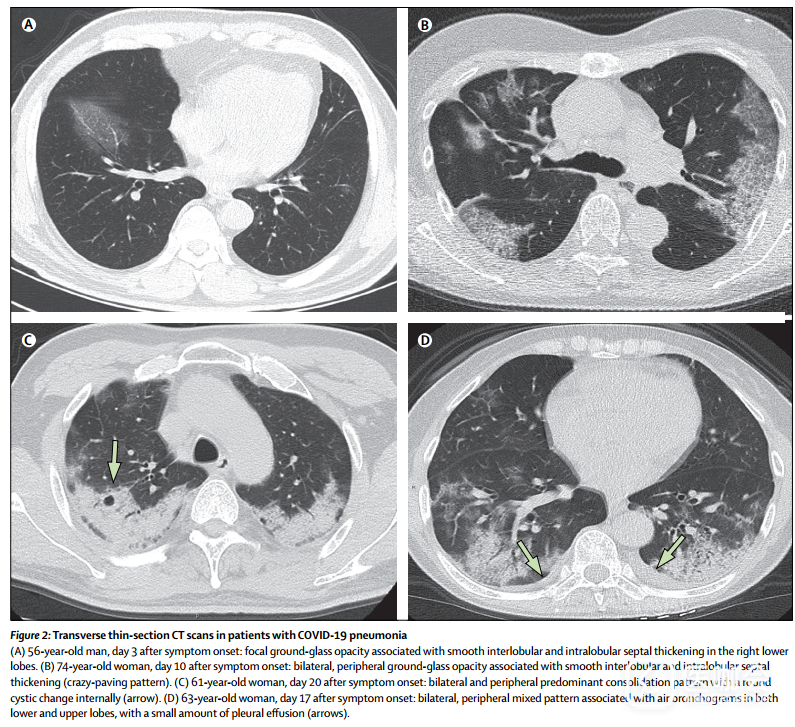

在这57例患者中,在所有CT扫描结果中观察到四种演变模式:最初就进展至峰值水平,其后影像学显示有所改善(1型),这种模式在26例(46%)患者中出现(图6),其中24例(92%)患者出院(住院中位时间为25天[IQR 20–27]); 影像学显示持续恶化(2型),包含18名患者(32%)(图5),其中2名(11%)患者死亡(患者2和3); 影像学显示逐步改善(3型),包含8名(14%)患者,其中5名(63%)出院(住院中位时间为19天[IQR 11-25]); 有5名(9%)患者的X线影像学表现没有变化(4型),他们在本研究的截止日期(2月8日)前仍在医院接受治疗。

图6 一名42岁女性的横向薄切片连续CT扫描影像(第一种演变模式)